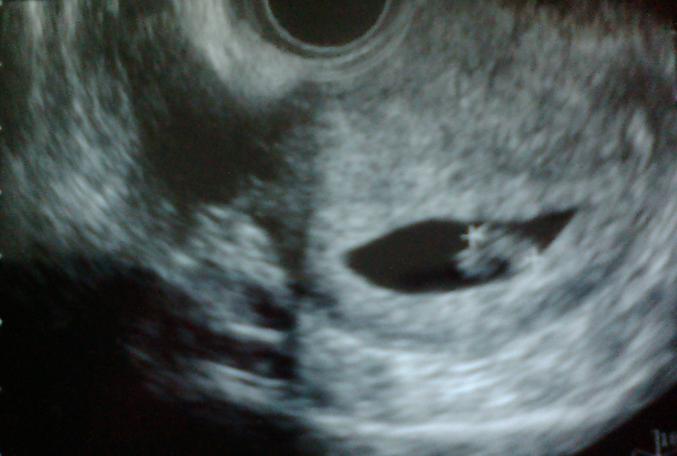

今回こそ心拍が確認できるかな?とドキドキでした^^;

無事にピコピコ動いてる心臓を確認できて本当に一安心

少し2頭身ぽくなってきたようです

前回は姿も見えてなかったのでずいぶん大きくなった気がします

大きさは『9.9mm』でした